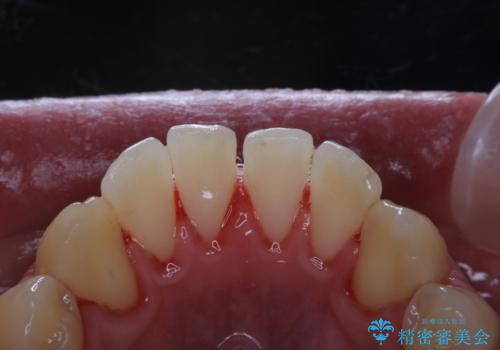

30代男性 PMTCで歯石取り

担当医 歯科衛生士